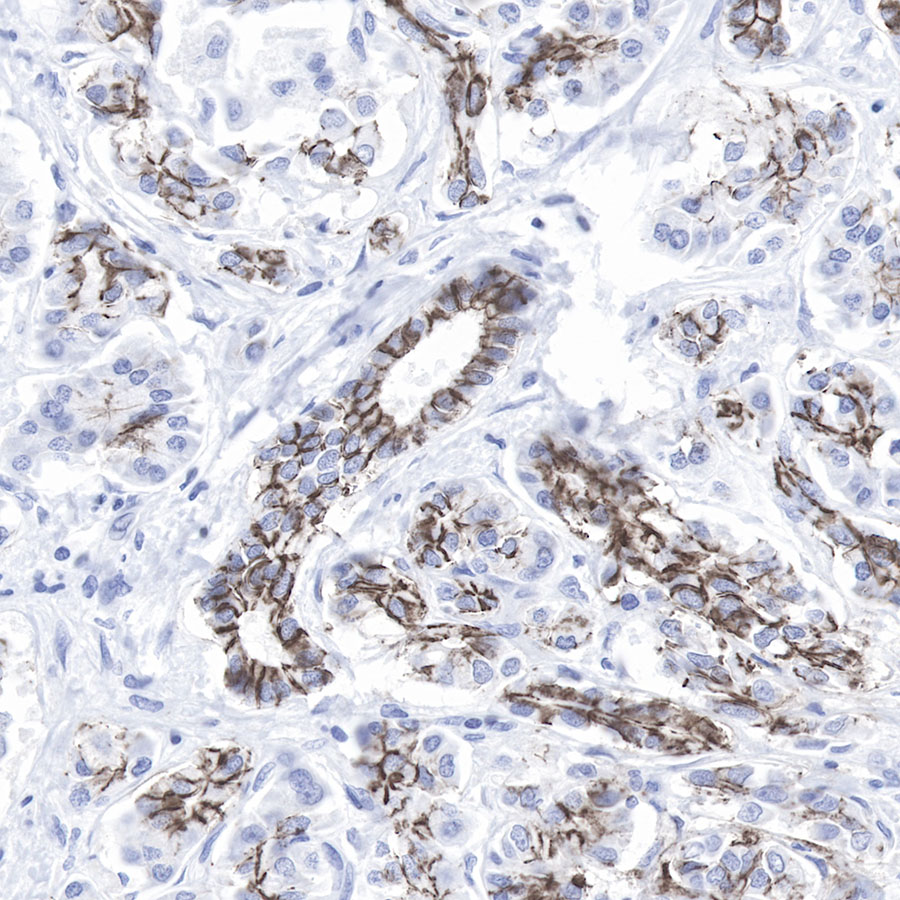

IHC shows positive staining in paraffin-embedded human colon cancer.

Anti-Claudin-1 antibody was used at 1/500 dilution, followed by a Goat Anti-Rabbit IgG H&L (HRP) ready to use. Counterstained with hematoxylin.

Heat mediated antigen retrieval with Tris/EDTA buffer pH9.0 was performed before commencing with IHC staining protocol.